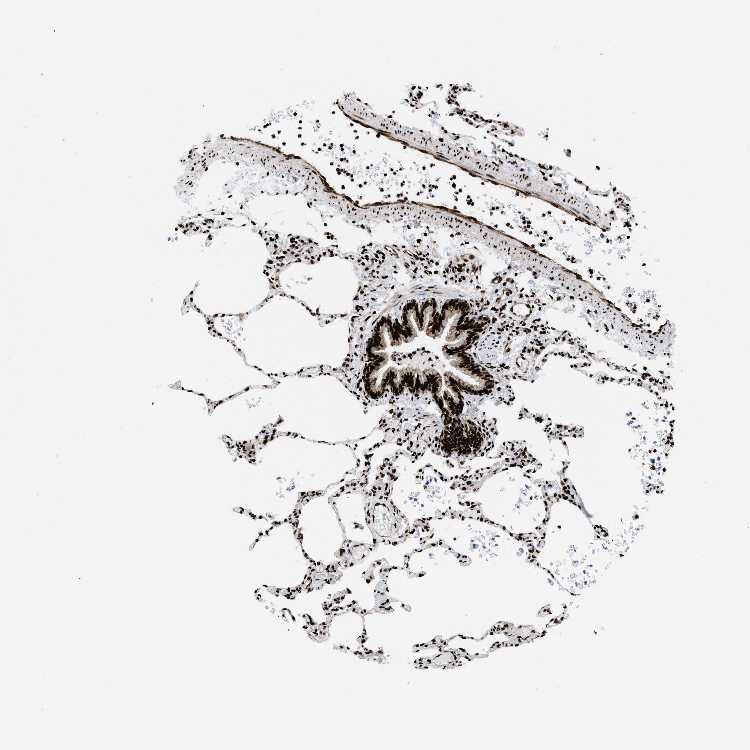

POLR2A